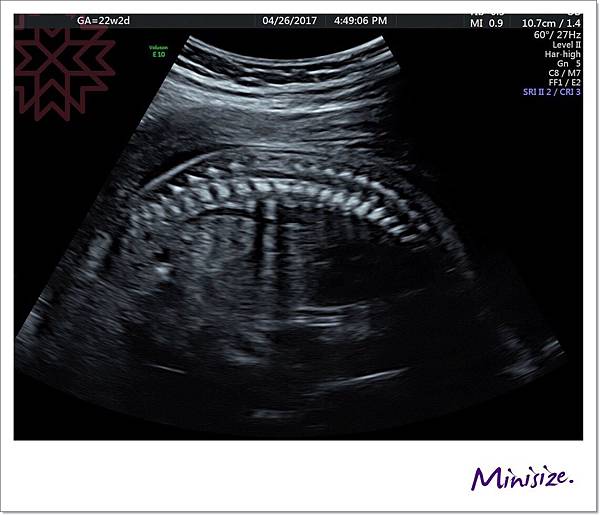

脊椎

骨骼要呈現排列整齊相互對稱

背部皮膚的表層也要光滑 完整連接